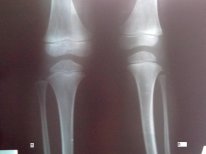

Я - Вишенка! Высылаю вам последние рентген-снимки.

посмотрите, пожалуйста.

Вишенка, приезжайте! С левой ноги 100% снятие аппаратов, на счёт правой ещё подумаем.

Здравствуйте, на рентгеновских снимках от 11.10.2011г. регенерат очень хорошей плотности. По этому можете спокойно брать билеты на конец месяца, в клинике придётся походить ещё одну недельку на распущенных аппаратах для "воспитания" костной мозоли. Поздравляю, всё идёт по плану!